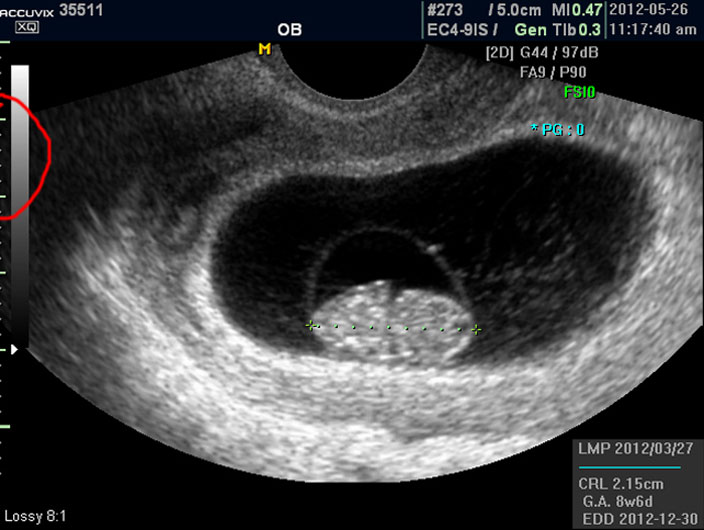

임신 8주 된 태아의 초음파 사진을 제대로 감상하는 방법을 설명드리겠습니다.

초음파 사진에서 살펴 볼 부분은 당연히 태아의 모습이겠지요.

그러나 임신 8주 정도의 초기에는 아직 아기가 쌀알 보다 조금 큰 정도이기 때문에 인간의 형체가 또렷하지는 않습니다.

그저 머리와 몸통 부분만 형성되어 있는 상태이지요.

우선 첫번째로 보이는 사진에서 가운데 하얗게 보이는 것이 태아입니다.

우측이 머리 부분이고 좌측이 몸통 부분이며 초기 임신에서는 아기 머리가 몸통의 반정도로 상당히 큰 상태입니다.

그리고 초음파 검사에서는 산전 초음파 이외의 다른 경우도 그렇지만 물에 가까운 성분일수록 검게 나오고 뼈처럼 단단해서 초음파 선이 투과하지 못하는 부분은 하얗게 나타납니다.

이는 투과 선은 다르지만 X 레이 검사 사진에서도 마찬가지입니다.

따라서 하얗게 보이는 태아 주변의 검은 부분은 양수입니다.

이 양수의 양은 아기의 건강과 밀접한 관련이 있기는 하지만 그 절대적 양을 측정하기는 어려워서 몇군데 부위를 체크하여 많은지 적은지를 판단합니다.

물론 임신 중기 이후 양수 과소증이나 양수 과다증이 의심될 경우이며 일반적으로는 1차원적으로 봤을 때 양수의 가장 긴 길이가 태아 크기의 2배에서 4배 정도의 길이를 차지하지만 이 길이나 양은 임신 주기에 따라 다르기 때문에 정확한 것은 아니며 또한 임신 말기로 갈수록 상대적으로 양수의 양이 줄어듭니다.

양수는 태아의 소변으로 만들어지고 태아가 폐나 위로 흡수해서 소멸하기 때문에 항상 변동이 되는 부분입니다.

양수 바깥의 조금 회색으로 보이는 얼룩덜룩한 부분이 아기를 품고 있는 자궁이며 근종이나 기타 이상은 없는지 체크하지만 여기서는 산과 부분만 설명하기로 했기 때문에 따로 설명드리지 않습니다.